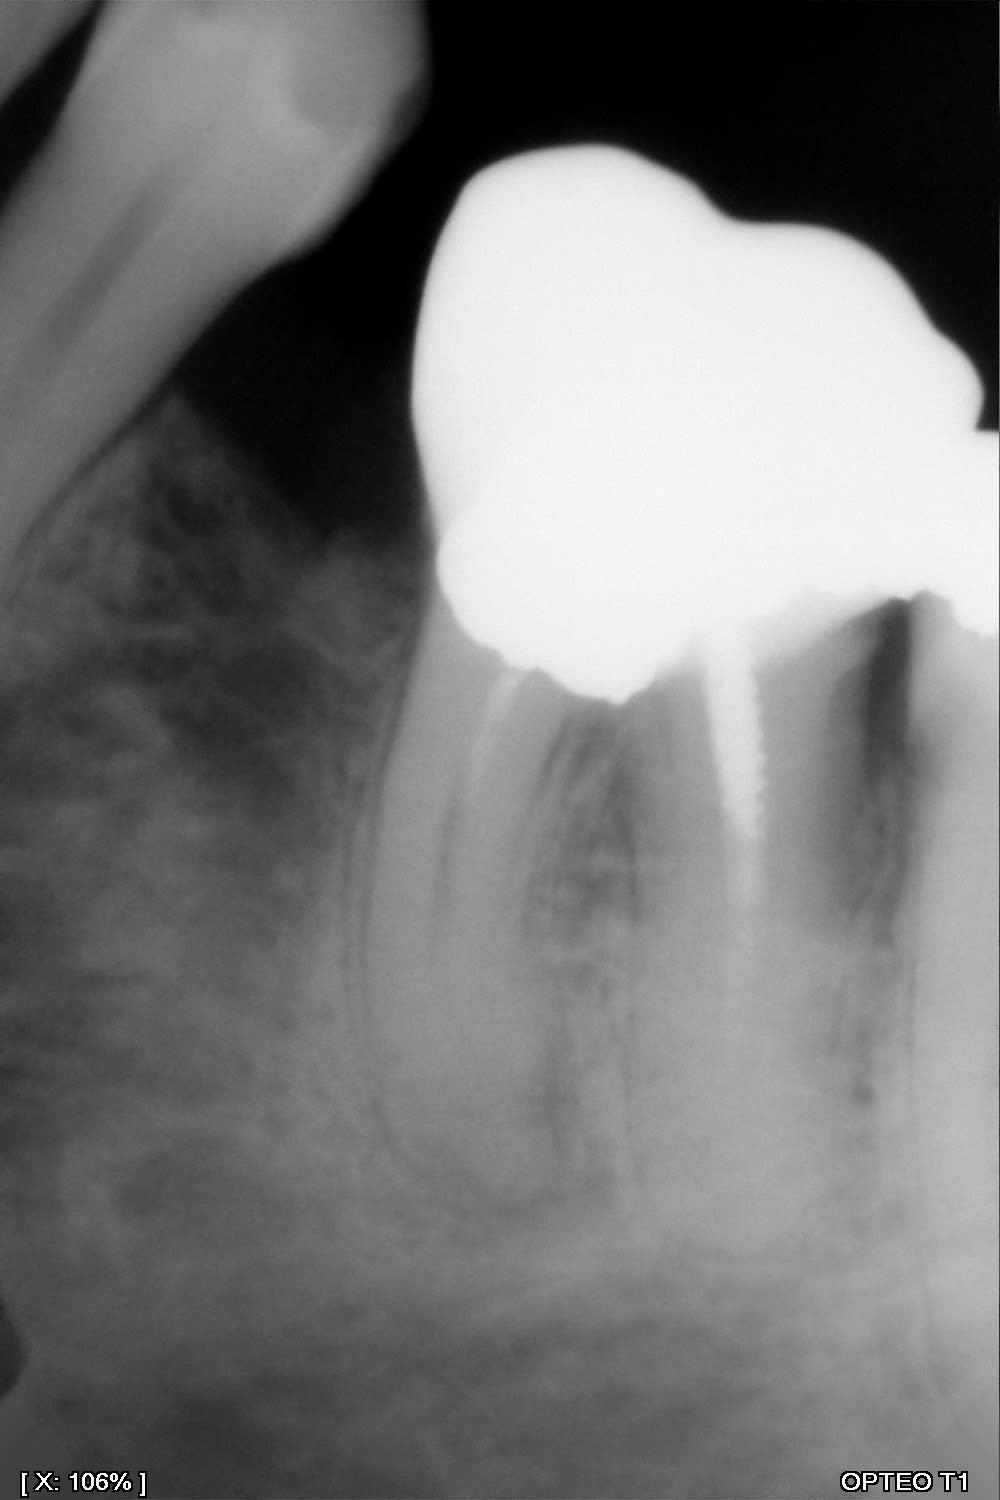

Comme Prunelles, d'autant plus qu'à la panoramique j'ai quand même bien l'impression qu'il y a une reprise carieuse sur 36.